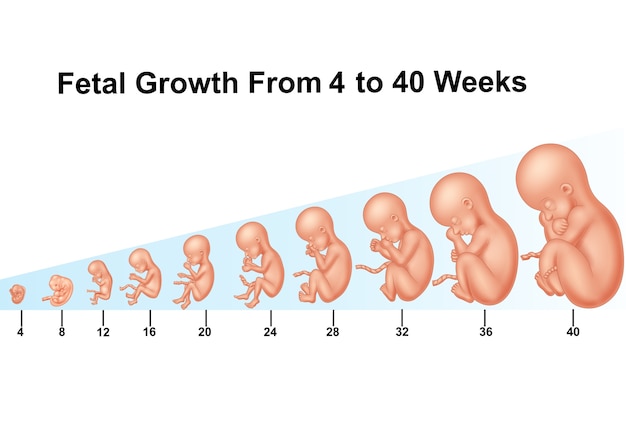

胎児の成長 , , ママの子宮に着床してから40週に入るまでの赤ちゃんの成長👶,お腹の中でこんなに成長してくれるので、ママのお腹はパツパツ💦🤰, ,お腹が圧迫されて息苦しかったり、気持ち悪かったり、便秘や頻尿になったり とママの身体は悲鳴をあげつつも子宮は立派に赤ちゃんを育ててくれます👏👏👏,, 出産されたママ、赤ちゃんを大切に育ててくれてくれてありがとう❣️,。

4週から40週までの胎児の成長Premiumベクトル素材。

胎児の成長過程と週数のイラスト素材103469027- PIXTA。

胎児の成長過程 妊娠初期・中期・後期の変化 FMF胎児クリニック東京ベイ幕張東京都・千葉県。